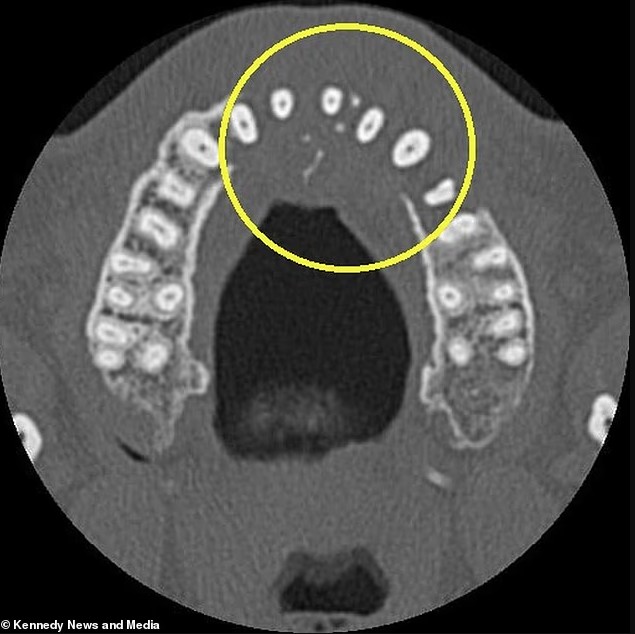

Mắc ungthư ở tuổi 24, cô gái kêu gọi người trẻ: Nếu thấy 3 dấu hiệu này, đừng bao giờ bỏ qua

Một cô gái trẻ đã chia sẻ những dấu hiệu cảnh báo của căn bệnh ung thư đại trực tràng giai đoạn 3, kêu gọi mọi người đừng bỏ qua các triệu chứng có thể báo hiệu bệnh nghiêm trọng. Bạn không bao giờ nên phớt lờ những thay đổi của cơ thể, ngay cả […]